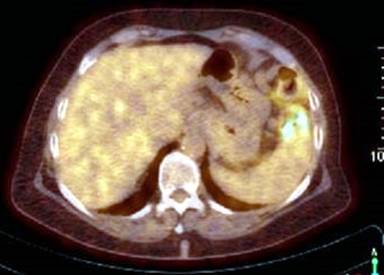

In January 2011 a 69-year-old female patient was admitted to our hospital due to persisting abdominal pain and elevated liver enzymes in the serum. Based on CT-scans (Figures 1 and 2) and laboratory diagnostics, adenocarcinoma of the pancreatic tail with multiple liver metastases was diagnosed. This diagnosis was confirmed histologically by biopsy of one of the liver metastases revealing poorly differentiated adenocarcinoma (Figure 3). Because of the clear constellation of diagnostic findings immunohistochemistry was dispensable. In our interdisciplinary tumor conference palliative chemotherapy was suggested. Because of the patients’ excellent performance status (ECOG 0) a first line therapy including folic acid, fluorouracil, oxaliplatin and irinotecan (FOLFIRINOX) was initiated in February 2011. In follow up staging CT scans showed significant shrinkage of the liver metastases and of the primary tumor, while serum CA 19-9 decreased concomitantly (Figure 4). After 2 years of chemotherapy, in February 2013, liver metastases could hardly be detected anymore, whereas the primary tumor in the pancreatic tail was still detectable and suspicious of residual cancer tissue. Thus, chemotherapy with FOLFIRINOX was continued. Subsequently, the lesion in the pancreatic tail stayed exactly the same size over another year of chemotherapy, while liver metastases did not recur as long as FOLFIRINOX was administered. In April 2014 we additionally performed an FDG-PET-CT-scan to find out whether the primary lesion in the pancreatic tail was still representing vital tumor tissue. Neither in the liver nor in the pancreatic tail FDG-uptake was increased (Figures 5, 6). Thus, we paused chemotherapy for 12 weeks and performed another CT-scan in August 2014 revealing a single metastasis in segment IVb of the liver. This metastasis was treated by radio frequency ablation (RFA). Six weeks later another CT-scan showed no sign of vital tumor tissue in the pancreas or the liver or elsewhere in our patient.

Figure 5. PET-CT-scan in May 2014. The blue arrow marks the pancreatic tail-region. |

Figure 6. PET-CT-scan in May 2014. No increased signal within the liver parenchyma is detectable. |